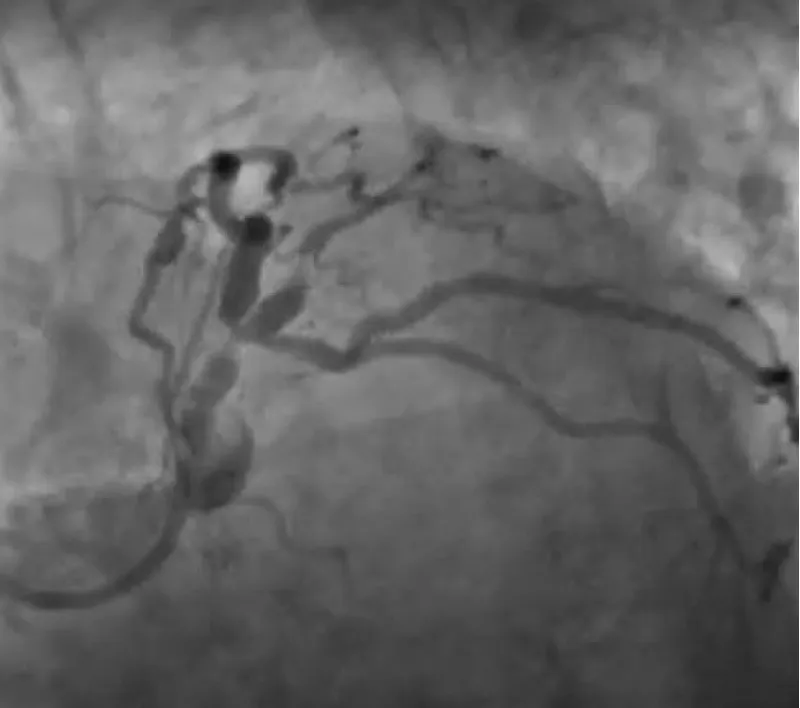

The clinical case concerns an 81-year-old woman with a history of systemic arterial hypertension, hypercholesterolemia, paroxysmal atrial fibrillation, chronic kidney disease, iron-deficiency anemia, and bilateral carotid atheromatosis for which she underwent a Carotid Endarterectomy (CEA) procedure. Additionally, she had a history of breast carcinoma, treated with surgery, subsequent chemotherapy, and ongoing Letrozole therapy. In 2019, the patient presented to the emergency department due to exertional dyspnea and low-threshold angina. During hospitalization, high average ventricular response (109 BPM) atrial fibrillation was diagnosed. Routine lab tests showed rising of hsTN-I (peak 800 pg/dL) and pro-BNP (peak 2476 pg/mL) and anemia Hb 9.1 g/dL. Echocardiography revealed severe depression of the left ventricular function (ejection fraction of 30%, with antero-apical akinesia) and low-flow-low-gradient aortic stenosis (mean gradient of 26 mmHg and AVAi of 0.5 cmq/m2 and SVi 29 mL/m2). So it was performed a Dobutamine stress Echo showed a rise of SVi up to 38 mL/m2 and a mean aortic gradient of up to 48 mmHg. Coronary angiography showed the right dominant coronary artery, of good caliber and course, with no angiographically significant lesions (Figure 1). The Left Main artery, with good caliber, had a 90% calcific stenosis at the distal segment, involving the proximal segment of the Left Anterior Descending artery. The Left Circumflex artery, with good caliber and course, presented a 30% ostial stenosis. The Intermediate Branch, with good caliber and course, showed 80% stenosis at the proximal segment (Figure 2). The Left Anterior Descending artery, also of good caliber and course, was diffusely atherosclerotic with a long, severely calcific 80% stenosis at the mid-distal segment (Figure 3). Therefore, the case was discussed by a multidisciplinary Heart team at our center. The STS score calculated indicated a mortality risk of 11.4%. Due to this high risk, surgical treatment was not considered, and the patient underwent a four-step percutaneous intervention. Before the intervention, a CT angiography was performed, revealing an aortic annulus area of 433.2 mm2, a perimeter of 75.3 mm, and a coronary height from the annulus of 10 mm. The right common femoral artery mean diameter was 6.1 mm2 and the external iliac artery was 8.4 mm2 with moderate tortuosity without significant calcification (Figure 4-6). Therefore, a 23 mm Edwards Sapien 3 valve was chosen. Our strategy consisted of 4 steps:

Figure 2: The Left Main artery, with good caliber, had a 90% calcific stenosis at the distal segment, involving the proximal segment of the Left Anterior Descending artery. The Left Circumflex artery, with good caliber and course, presented a 30% ostial stenosis. The Intermediate Branch, with good caliber and course, showed 80% stenosis at the proximal segment.